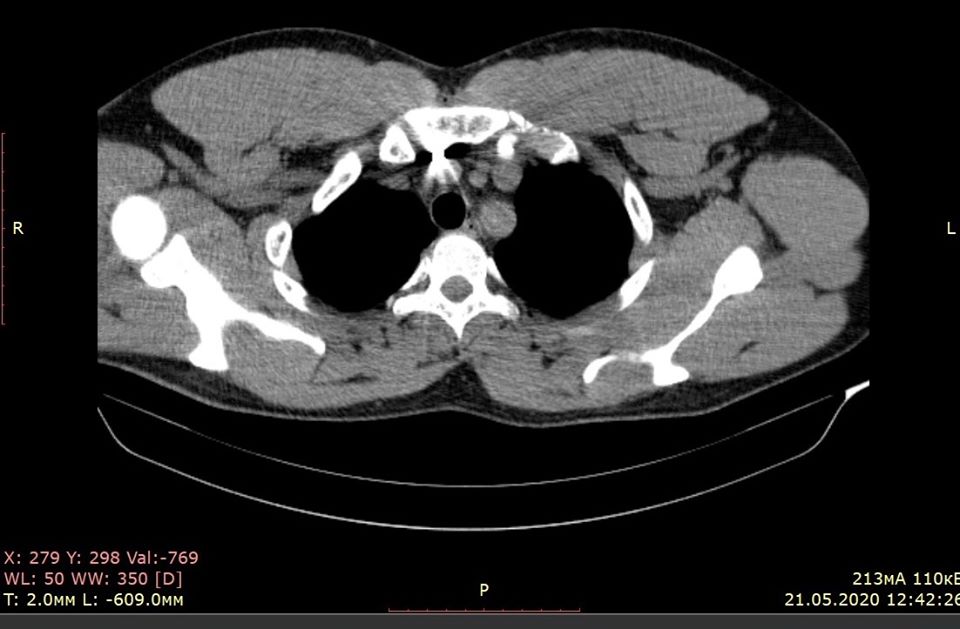

"На полдороги к бездне. Офицеры. Сергею 33. Его тело "нафаршировано" осколками. Взрыв противопехотной мины (черная вдова) забрал друга-командира (полковника полиции Сергея Губанова). Большой шрам на груди после операции - вечное напоминание о войне. Осколок лежал на аорте вблизи сердца. Лучшие торакальные хирурги Глеб Шкарупа и Андрей Снисарь провели блистательную операцию в больнице Мечникова", - отметил он.